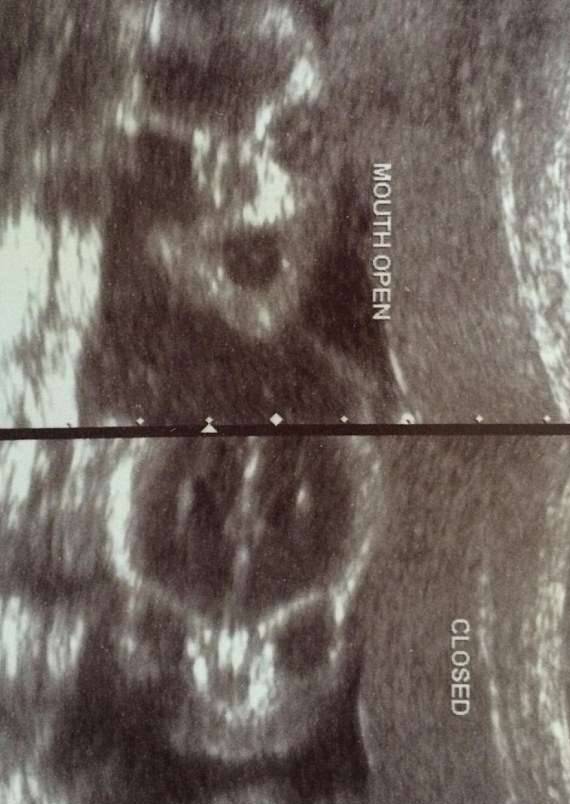

▼妈妈看到这画面应该会瞬间沈默吧。